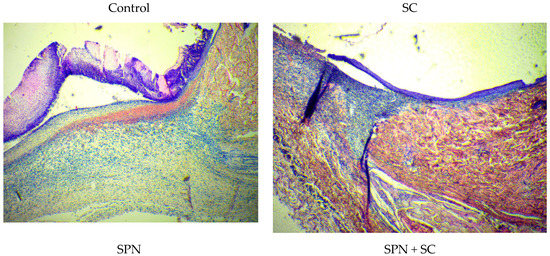

A decrease in leukocyte infiltration in the treatment groups was associated with the most rapid transition from exudation to proliferation. This was confirmed by the following histological signs. First, on day 3, all wounds were covered with a scab, which was soaked in polymorphonuclear leukocytes. The scab was thicker in the control group and thinner in the SC and SPN + SC groups. Second, the leukocyte infiltrates spread widely into the granulation tissue. This was most characteristic of the control group. Thirdly, in the tissues of all wounds, signs of a venous plethora of hypodermis were found, as well as the phenomenon of “marginal pool of leukocytes”. This phenomenon manifested itself in the accumulation of leukocytes in the parietal layer of the blood of postcapillary venules. This indicates the continuation of the migration process of leukocytes into the paravasal tissue, which is typical for the stage of exudation of inflammation. The lowest degree of edema and marginal leukocyte pool was recorded in the SPN + SC group (Figure 10).

Figure 10.

Center of wounds in different groups on the third day of the study (staining with Hematoxylin–Eosin, magnification ×100).